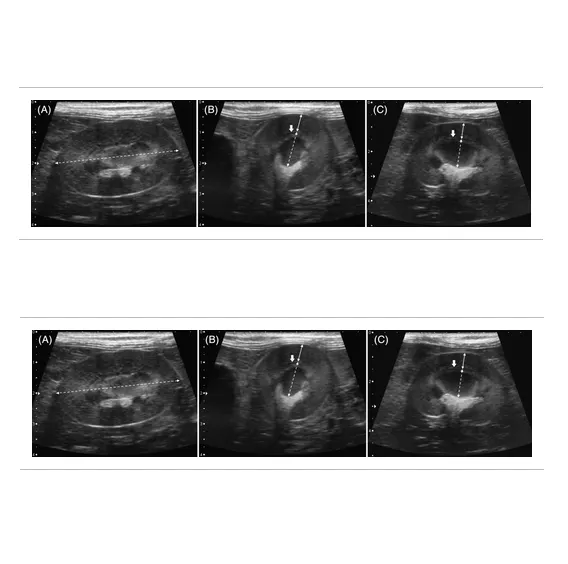

回溯性分析15隻IRIS第一到二級的貓、15隻三到四級的貓以及19隻健康的對照組。比較不同腎病分級的貓是否有皮質或髓質厚度的差異。以dorsal和transverse plan掃左右腎,腎臟被膜內緣量到arcuate blood vessel是皮質,而皮髓質交界的arcuate blood vessel到crest之前則是髓質。每個角度重複掃三次取平均值,盡可能地客觀。

腎臟皮質變薄和腎功能下降有相關性,而左側腎臟皮質4.7mm及右側腎臟皮質4.5mm可以作為是否有慢性腎病的分水嶺,有很高的敏感性與特異性 (sen90%, spc 83.3%/ sen94.7%, spec 94.7%)。此外,腎臟皮質的厚度並不會受年齡、體重、性別影響,可以搭配其他症狀與臨床病理結果來使用,比原本的腎臟大小好用得多。